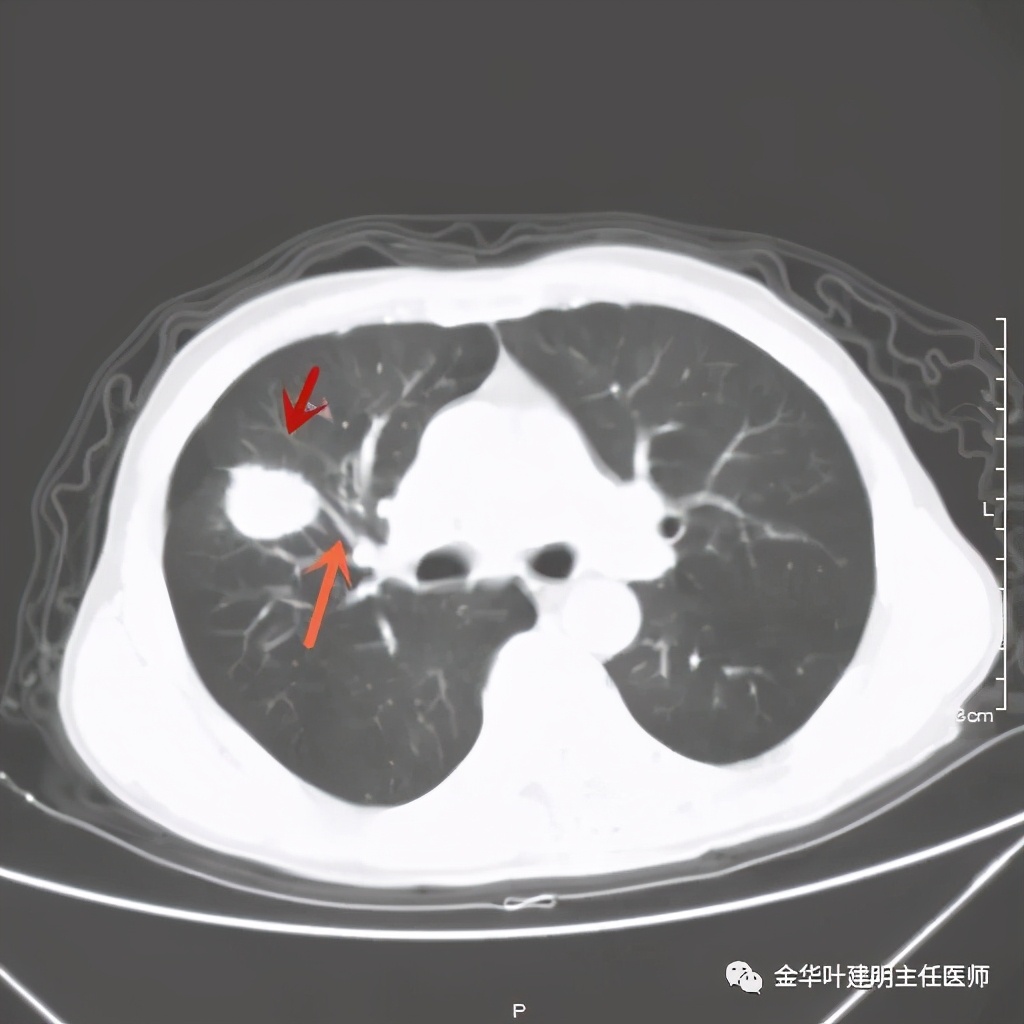

上图桔色箭头示血管进入病灶,较粗;紫色箭头示病灶与胸膜间似乎有所牵拉;红色箭头示病灶

上图桔色箭头示血管进入;红色箭头示病灶